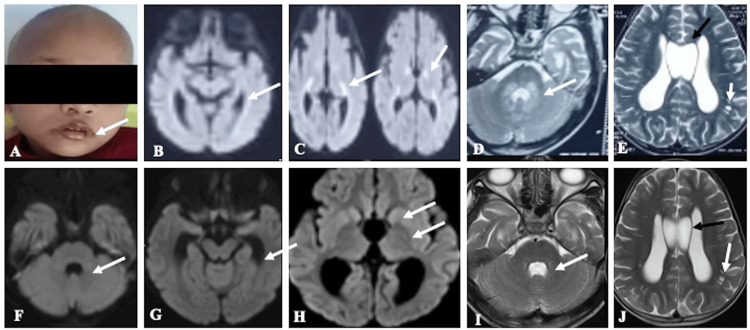

A six-year-old male child, born to non-consanguineous parents, presented with a one-week history of breathlessness. Breathlessness was gradual in onset and progressive in nature. The child was hospitalized outside, where he developed erythema around the eyes and perioral region (Figure 1A), which was gradually progressing, after which he was referred to our hospital. The child had multiple episodes of seizures previously since the age of 10 months and was on valproate till three years of age, and then tapered and subsequently stopped as he was seizure-free till the current presentation. No specific diagnosis was made at the hospital where he was treated. His antenatal and perinatal history was uneventful. Family history was noncontributory. His developmental milestones were appropriate for his age. Other past histories include brainstem evoked response audiometry (BERA) screening, which was positive for bilateral sensorineural hearing loss, hair loss for the past three months, and difficulty in walking for the past three months. On examination, he was conscious, irritable, oriented, afebrile, and hyperventilating (respiratory rate was 45/min). The rest of the vitals were normal, with SpO2 at 97% on room air. Generalized non-scarring alopecia, periocular erythema, and stomatitis were evident on examination. His height was between the third and tenth centiles. The rest of the anthropometric measurements were within limits. Chest examination was unremarkable. CNS and eye examinations were normal, with no meningeal or cerebellar signs. Initially, the possibility of an inborn error of metabolism-such as biotinidase deficiency, holocarboxylase synthetase deficiency, or a mitochondrial disorder-was considered in view of recurrent seizures with dermatological features in the form of alopecia with rashes. In the initial screening for IEM, venous blood gas analysis revealed combined respiratory alkalosis and metabolic acidosis, with a pCO₂ of 5 mmHg, HCO₃⁻ of 6 mmol/L, and lactate of 5.2 mmol/L. There was severe metabolic acidosis with CO₂ washout. Urinary ketone was positive. However, his blood sugar and electrolytes were within normal limits. Serum ammonia and creatinine phosphokinase levels were normal (Table 1). He was started on bicarbonate correction following the resolution of metabolic derangement. The breathlessness was secondary to acidotic breathing, which resolved after starting bicarbonate correction. He was started on a low-protein diet with biotin supplements orally at a dose of 10 mg/day, considering the possibility of treatable conditions like biotinidase deficiency. Cheilitis also showed improvement with biotin supplementation and multivitamins. Venous blood gas parameters normalized after initiation of treatment, and the patient improved symptomatically; therefore, repeat serum biotinidase activity testing was not performed. Magnetic resonance imaging (MRI), performed at an outside center, was reviewed in a multidisciplinary committee. The images revealed areas of restricted diffusion involving the genu and posterior limbs of both internal capsules, periventricular white matter adjacent to the lateral ventricles, and T2-weighted hyperintensities surrounding the fourth ventricle, with involvement of the dorsal pons, bilateral middle cerebellar peduncles, and dentate nuclei (Figures 1B–1E). Dilated Virchow-Robin spaces (VRS) and a cavum septum pellucidum (CSP) were also noted (Figure 1E). Based on the imaging and clinical presentation, biotinidase deficiency and holocarboxylase synthetase deficiency were considered the primary differential diagnoses.

Follow-up MRI performed two weeks later demonstrated complete resolution of the previously noted diffusion restriction (Figures 1F–1H) and minimal residual T2 hyperintensities around the fourth ventricle, with persistent dilated VRS and CSP (Figures 1I, 1J). Tandem mass spectrometry confirmed biotinidase deficiency, with serum biotinidase activity measuring less than 10% of normal (0.01 nmol/min/mL). Clinical exome sequencing and mitochondrial genome analysis were not pursued due to financial constraints. The child was discharged with appropriate dietary modifications, including a protein-restricted diet and supplementation with biotin, carnitine, pyridoxine, and oral bicarbonate. Use of a hearing aid was advised, along with regular clinical follow-up.